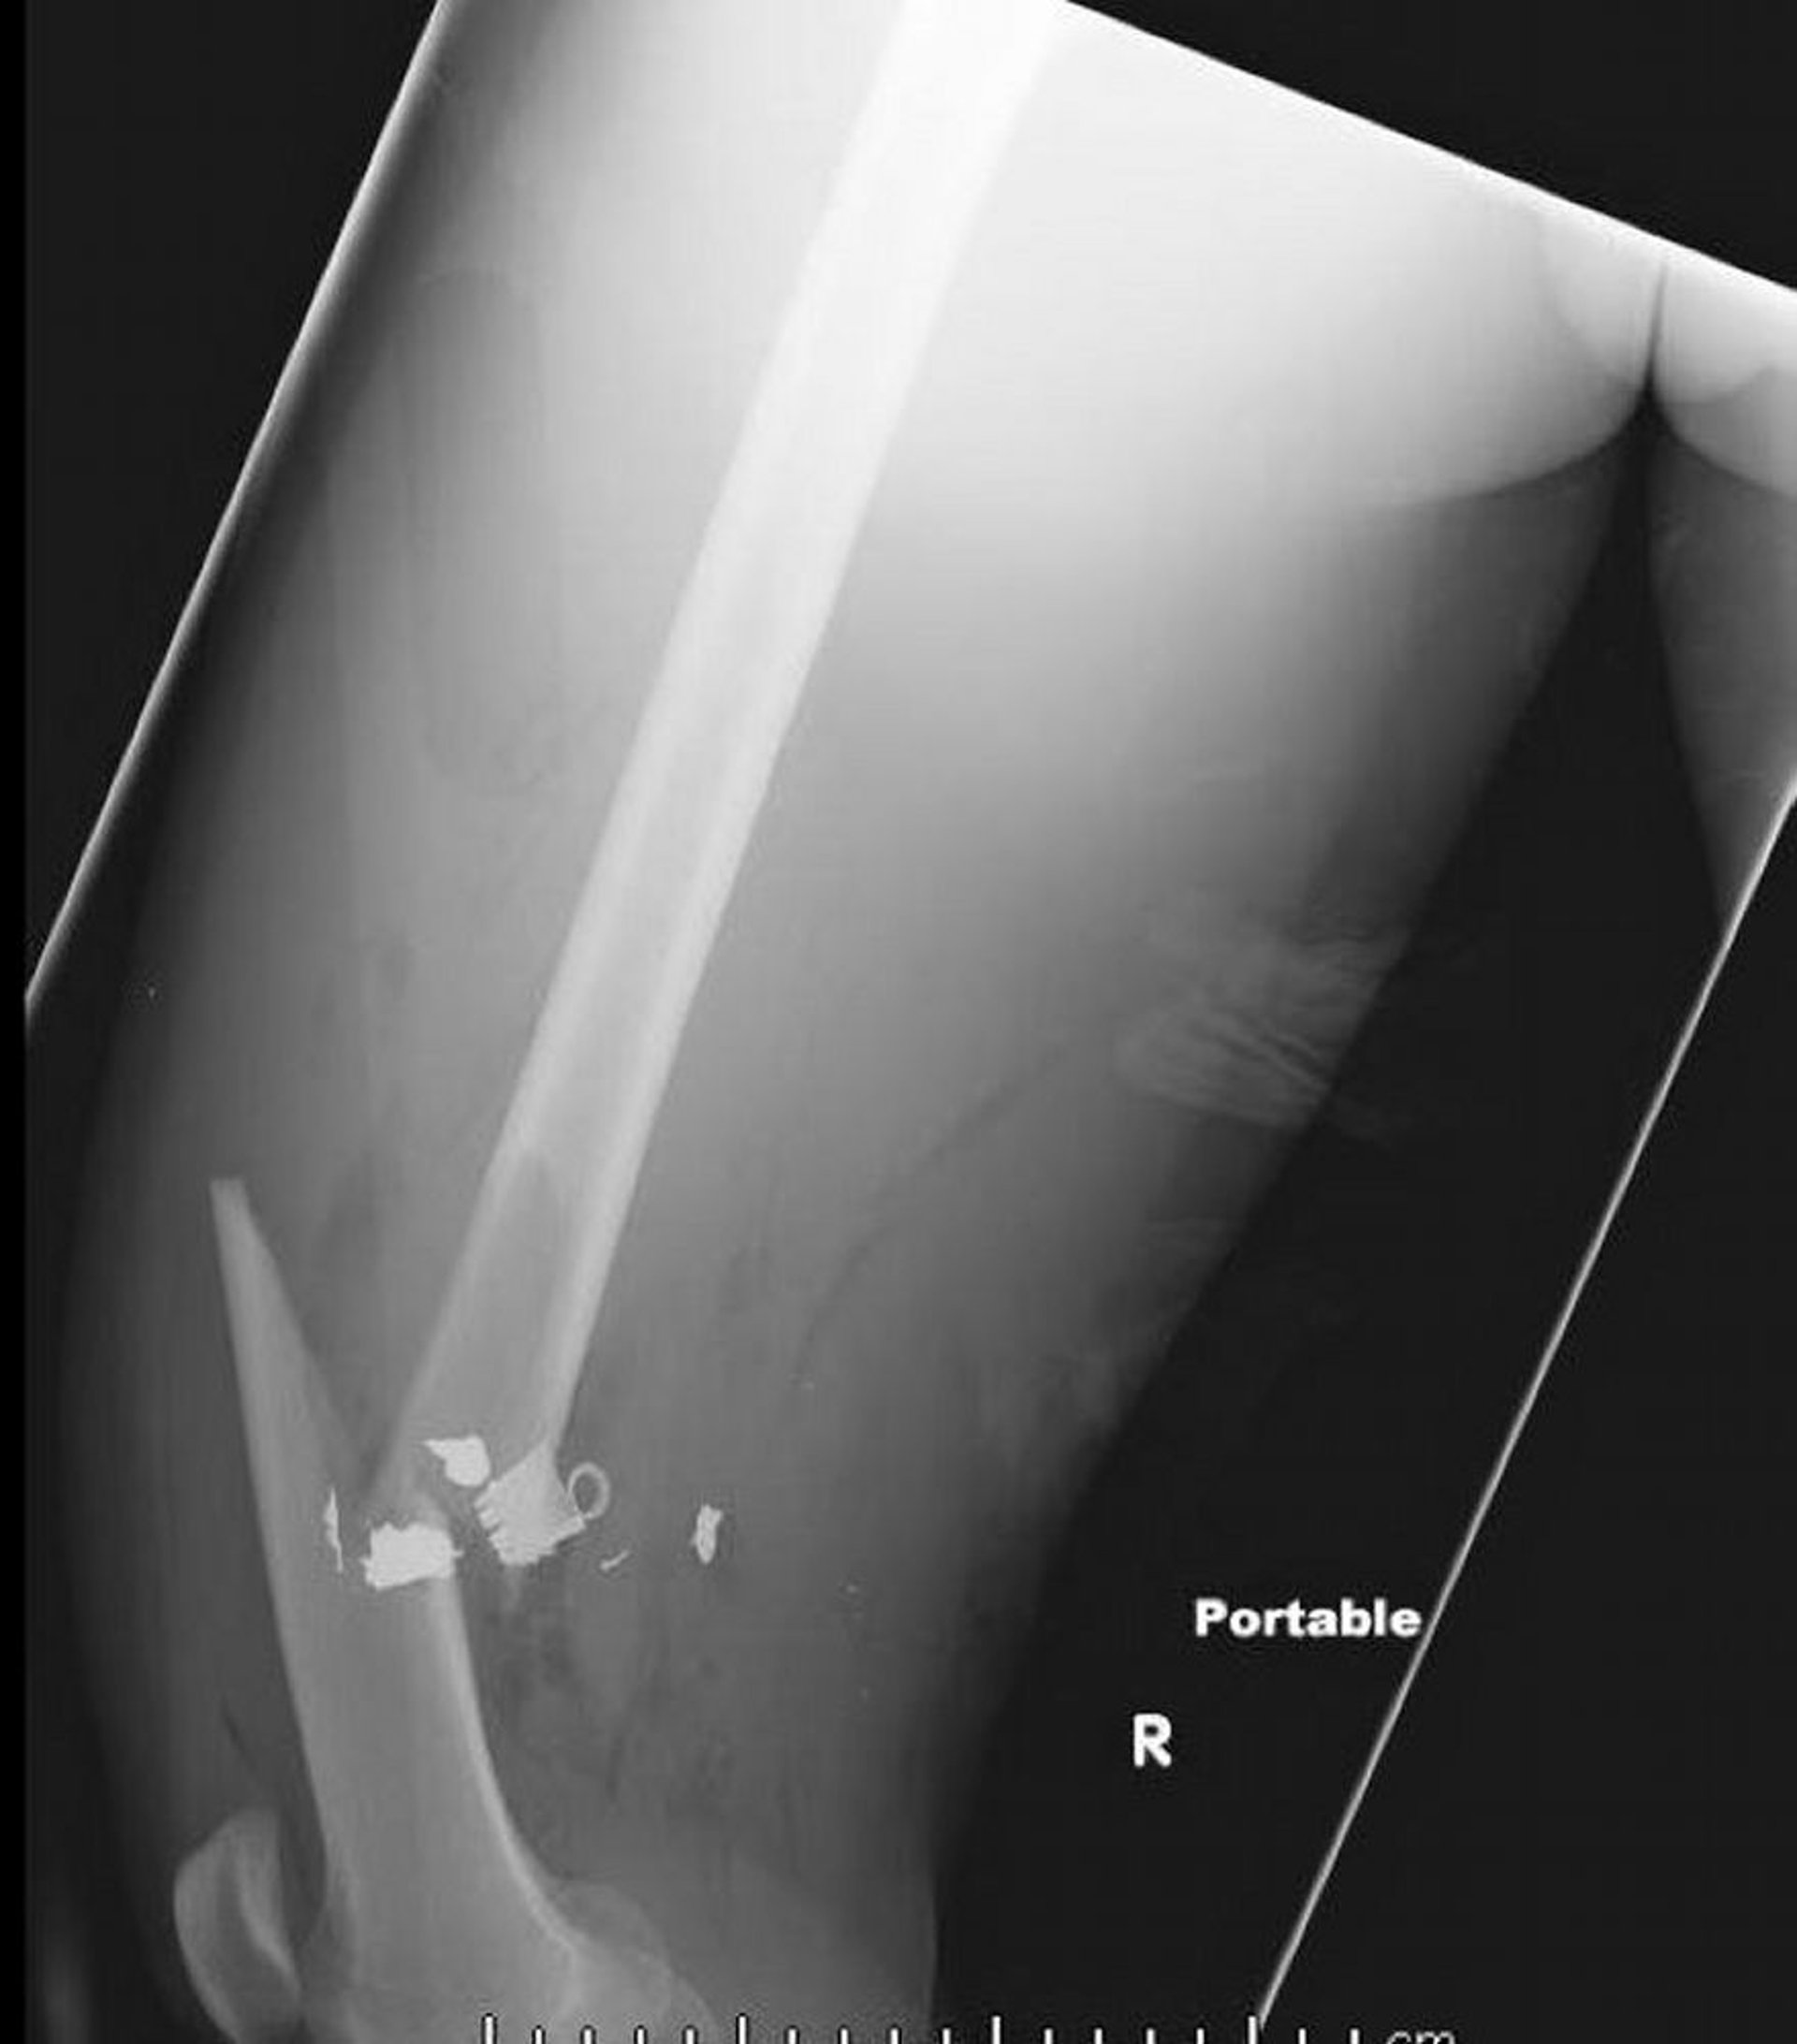

Fratura da diáfise média do fêmur (2)

Essa radiografia lateral do fêmur mostra uma fratura da diáfise média do fêmur com ar em tecidos moles e retenção de corpos estranhos de densidade metálica.